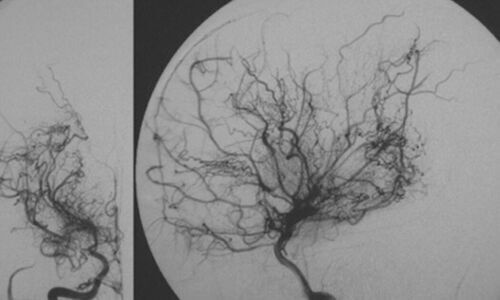

MIND MATTERS - Depression and moyamoya disease

Dr Shyamanta Das Moyamoya is a chronic, progressive, occlusive disease of blood supply to the brain and is often an important cause of stroke at a young age. Congenital rubella syndrome consists of sensorineural hearing defects, eye abnormalities such as cataract, microphthalmia, and retinopathy,...